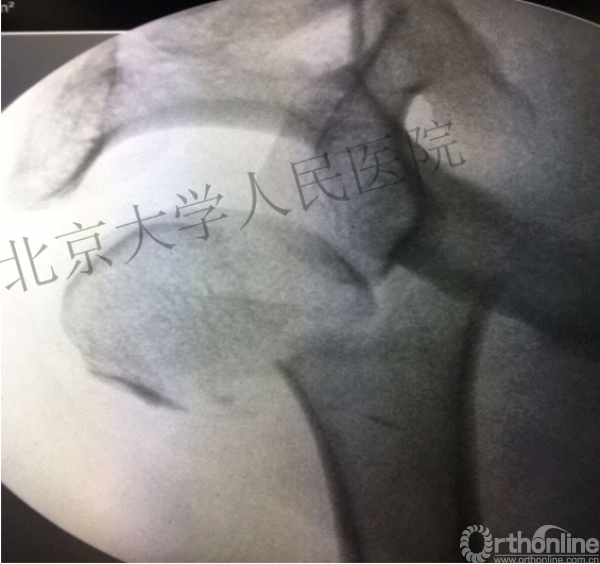

肱骨头复位

克氏针的应用“joystick”

简单骨折的闭合复位技术:以克氏针作为“joystick”

髓内钉的应用复位是关键

复位良好的标准:颈干角:135°,大结节与肱骨头距离:8mm